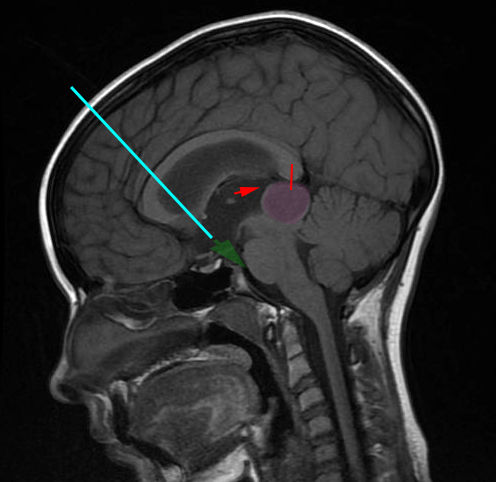

Η ενδοσκοπική τρίτη κοιλιοστομία είναι η διάνοιξη μιας μικρής οπής στο έδαφος την 3ης κοιλίας του εγκεφάλου προκειμένου να παροχετευθεί εγκεφαλονωτιαίο υγρό (Ε.Ν.Υ) από το κοιλιακό σύστημα στις βασικές δεξαμενές του εγκεφάλου . Είναι μια επέμβαση που πραγματοποιείται σε ασθενείς με αποφρακτικό υδροκέφαλο ως εναλλακτική λύση, σε ορισμένες περιπτώσεις, στην τοποθέτηση κοιλιοπεριτοναϊκής βαλβίδας εγκεφάλου. Το κύριο πλεονέκτημα της είναι η απουσία εξάρτησης από το κοιλιοπεριτοναϊκό σύστημα παροχέτευσης του Ε.Ν.Υ. |

Η επέμβαση γίνεται με τον ασθενή υπό γενική αναισθησία. Η προσπέλαση στο κοιλιακό σύστημα του εγκεφάλου γίνεται μέσω μικρής κρανιοτομίας, συνήθως δεξιά μετωπιαία, και με την βοήθεια ενδοσκοπίου. Η οπή από την οποία παροχετεύεται το Ε.Ν.Υ. γίνεται στο έδαφος της τρίτης κοιλίας του εγκεφάλου με την βοήθεια ειδικού καθετήρα.